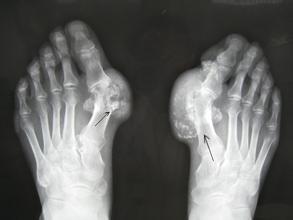

痛风的危害体现在哪些方面呢?在骨科疾病中,痛风是一种较为难治疗的疾病,而且该疾病会严重影响患者的身心健康,若不能及时进行治疗,会导致更严重的后果,那么,痛风的危害体现在哪些方面呢?针对这个问题,我们看看权威专家介绍的详细内容吧。